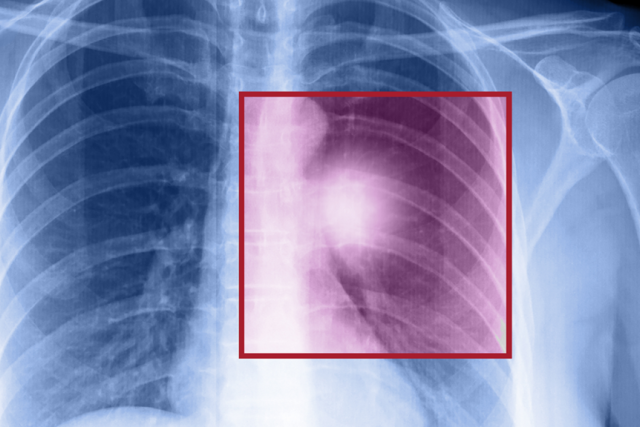

Lung cancer is the top-killing cancer among Americans, but certain high-risk people who have smoked, or currently smoke, can undergo a low-dose CT lung scan that reduces death rates by at least 20%.

“Lung cancer deaths exceed deaths from breast, prostate and colon cancer combined,” says Denise Aberle, MD, a diagnostic radiologist at UCLA Health. “We now have a screening test that can detect lung cancer in asymptomatic individuals, potentially at its earliest stage when local therapy can be curative.”

Key findings

A dedicated chest radiologist examines nodules in the lungs for any that could be cancerous based on size and density of the nodule. Potential lung cancer is missed infrequently but the greater concern is a false positive for a nodule that is not lung cancer but requires further testing.

Abnormal results

Standardized guidelines have been developed by an expert committee in the American College of Radiology. UCLA Health follows those guidelines to manage lung nodules based on their size and consistency.

A large nodule could call for a biopsy or a PET-CT scan to look for cancer. Roughly 12% of all patients need some form of additional testing, but in the majority of cases, this only involves getting a follow-up low dose CT scan to ensure that the nodule does not change.